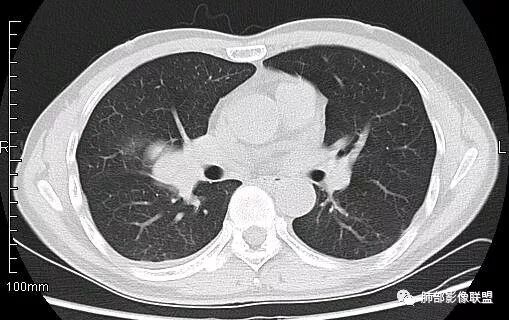

南边:从叶裂的变形,下朝上,越来越朝前扭曲,提示叶裂局部有朝前上推移的趋势

南边:病灶边界清,提示侵袭性弱,膨胀生长为主;这时候我们提示病灶不应该是支气管关系密切,提示间叶来源或胸膜来源

3.肿块常常较大,甚至巨大,病灶边界一般清楚,影像上常有假包膜样结构、有膨胀性生长的特点,影像科医师有时甚至会纠结其来源于肺部或是胸壁纵隔。常见的肺癌肿块,很少有机会能长成这样的规模。

4.边缘可以有浅切迹,部分病灶会有铸型样外观,但大体十分圆钝,不会出现典型的分叶和毛刺,也很少会出现胸膜牵拉。支气管常推移,有明显的支气管阻塞时也较少观察到相关的阻塞性炎症。

3.PPS在肺实质内成膨胀性生长,很少侵犯或突破支气管黏膜,影像学表现密度均匀、边缘光整的肿块,少有空洞、分叶、毛刺、钙化,一般为单发,体积较大,直径多在4cm以上,增强后呈不均匀强化。